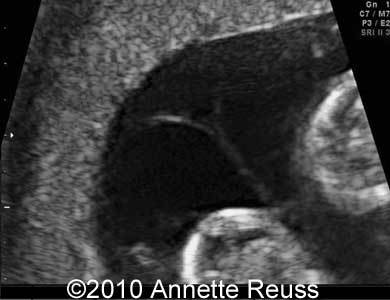

Qual sinal USG de gestação Dicoriônica?

SINAL DO Y (lambda)